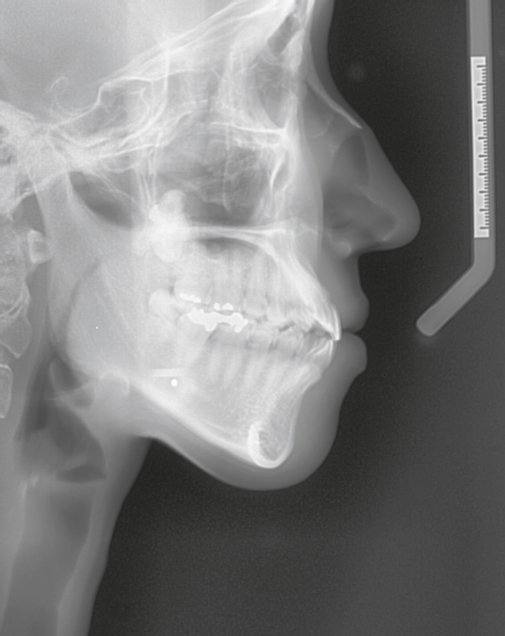

The glabellar and nasal root region shows a wide range of variation even in Asians. Therefore, the proximal implant should be carved carefully according to individual anatomy to fit in this area. Preoperative X-ray may be helpful for visualization of the bone and soft tissue anatomy of this area (Fig. 2.2). Examination by manual palpation of this area before or during the operation is also very important.